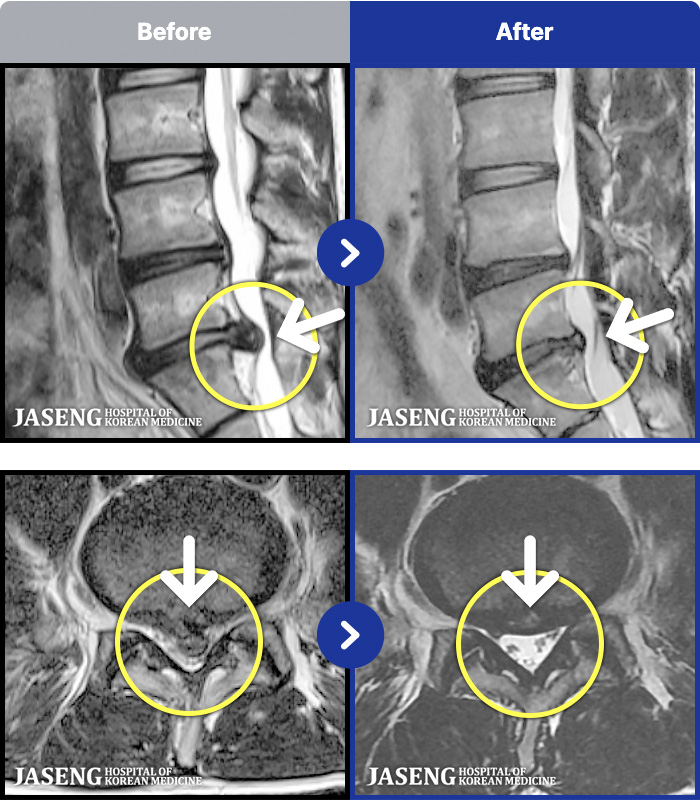

54 MRI ũ ʸ Ȯϼ.

[뱸] 19.11.28~25.05.06